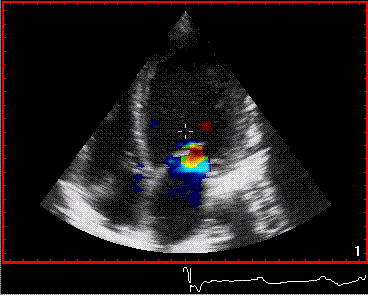

Manchmal müssen Ärzte die Wellenform des Blutflusses genau beobachten, und wenn sie ihre Geschwindigkeit messen, wechseln sie zu einem anderen Ultraschall: Doppler-Ultraschall. Schwangere Mütter kennen dreidimensionale undvierdimensionaler Ultraschall.